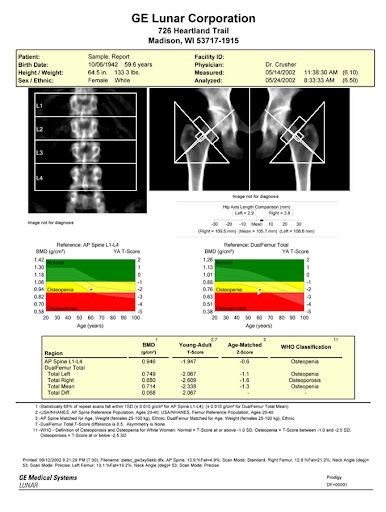

Sample DEXA Scan Report from Measure Up